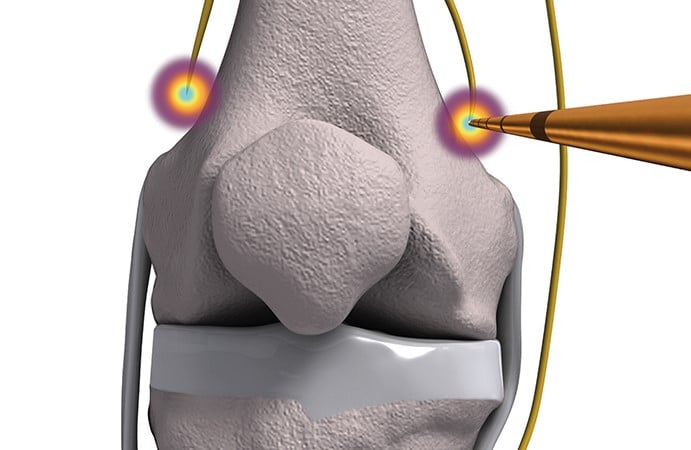

- درد زانو (اعصاب ژنیکولار)

توانبخشی با رادیوفرکوئنسی با کمک هدایت فلوروسکوپی انجام میشود. فلوروسکوپ یک دستگاه پرتونگاری است که به پزشک اجازه میدهد هنگام انجام عمل ، در واقع یک تصویر با اشعه ایکس را مشاهده کند. این به پزشک اجازه میدهد تا وقتی که قرار است سوزن الکترود به صورت دقیق و کامل در محل مورد نظر قرار بگیرد، مشاهده کند. استفاده از فلوروسکوپی قرار دادن الکترود را در محل مورد نظر بسیار ایمن تر و دقیق تر میکند. در انجام توانبخشی با رادیوفرکوئنسی ، پزشک شما الکترود سوزنی را در نزدیکی مفصل فاست قرار میدهد تا نوک سوزن در نزدیکی عصب شاخه میانی که به مفصل می رود بسیار نزدیک باشد. هنگامی که پزشکتان مطمئن شد که نوک سوزن در جای مناسب قرار دارد ، نوک سوزن برای احتیاط و تخریب عصب گرم میشود. هنگامی که اعصاب حسی از مفاصل دردناک از بین میروند ، باید درد شما کاهش یابد.